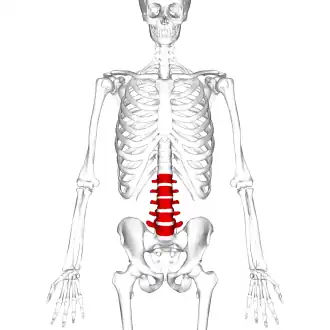

Position of human lumbar vertebrae (shown in red). It consists of 5 bones, from the top down, L1, L2, L3, L4 and L5. | |

The lumbar vertebrae are located between the thoracic vertebrae and pelvis. They form the lower part of the back in humans, and the tail end of the back in quadrupeds. In humans, there are five lumbar vertebrae. The term is used to describe the anatomy of humans and quadrupeds, such as horses, pigs, or cattle. These bones are found in particular cuts of meat, including tenderloin or sirloin steak.

In human anatomy, the five vertebrae are between the rib cage and the pelvis. They are the largest segments of the vertebral column and are characterized by the absence of the foramen transversarium within the transverse process (since it is only found in the cervical region) and by the absence of facets on the sides of the body (as found only in the thoracic region). They are designated L1 to L5, starting at the top. The lumbar vertebrae help support the weight of the body, and permit movement.

3D image of a lumbar vertebra Position of lumbar vertebrae (shown in red). Animation.

Position of lumbar vertebrae (shown in red). Animation. Same as the left. Bones around the lumbar vertebrae are shown as semi-transparent.